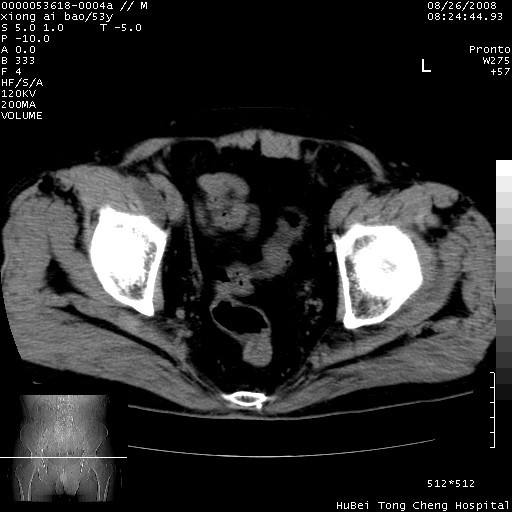

标题: CT15583:M,53Y。请老师指教分析骨盆及其他病变。 [打印本页]

标题: CT15583:M,53Y。请老师指教分析骨盆及其他病变。

股骨头坏死/腹股沟疝。

双侧股骨头无菌坏死,左侧腹股沟斜疝。

非常典型病例,双侧股骨头坏死伴双髋关节周围软组织肿胀,左腹股沟疝。

双侧股骨头坏死伴双髋关节周围软组织肿胀,左腹股沟疝。

双侧骨股头无菌性坏死,左侧腹股沟疝

双侧髋关节肿胀明显,感觉还不能排除结核。

考虑双侧髋关节结核,左侧腹股沟疝